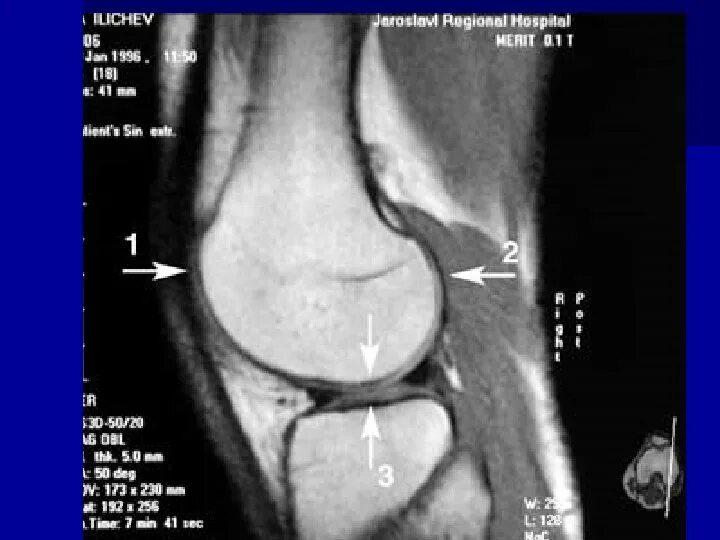

Что такое синовит коленного сустава на мрт